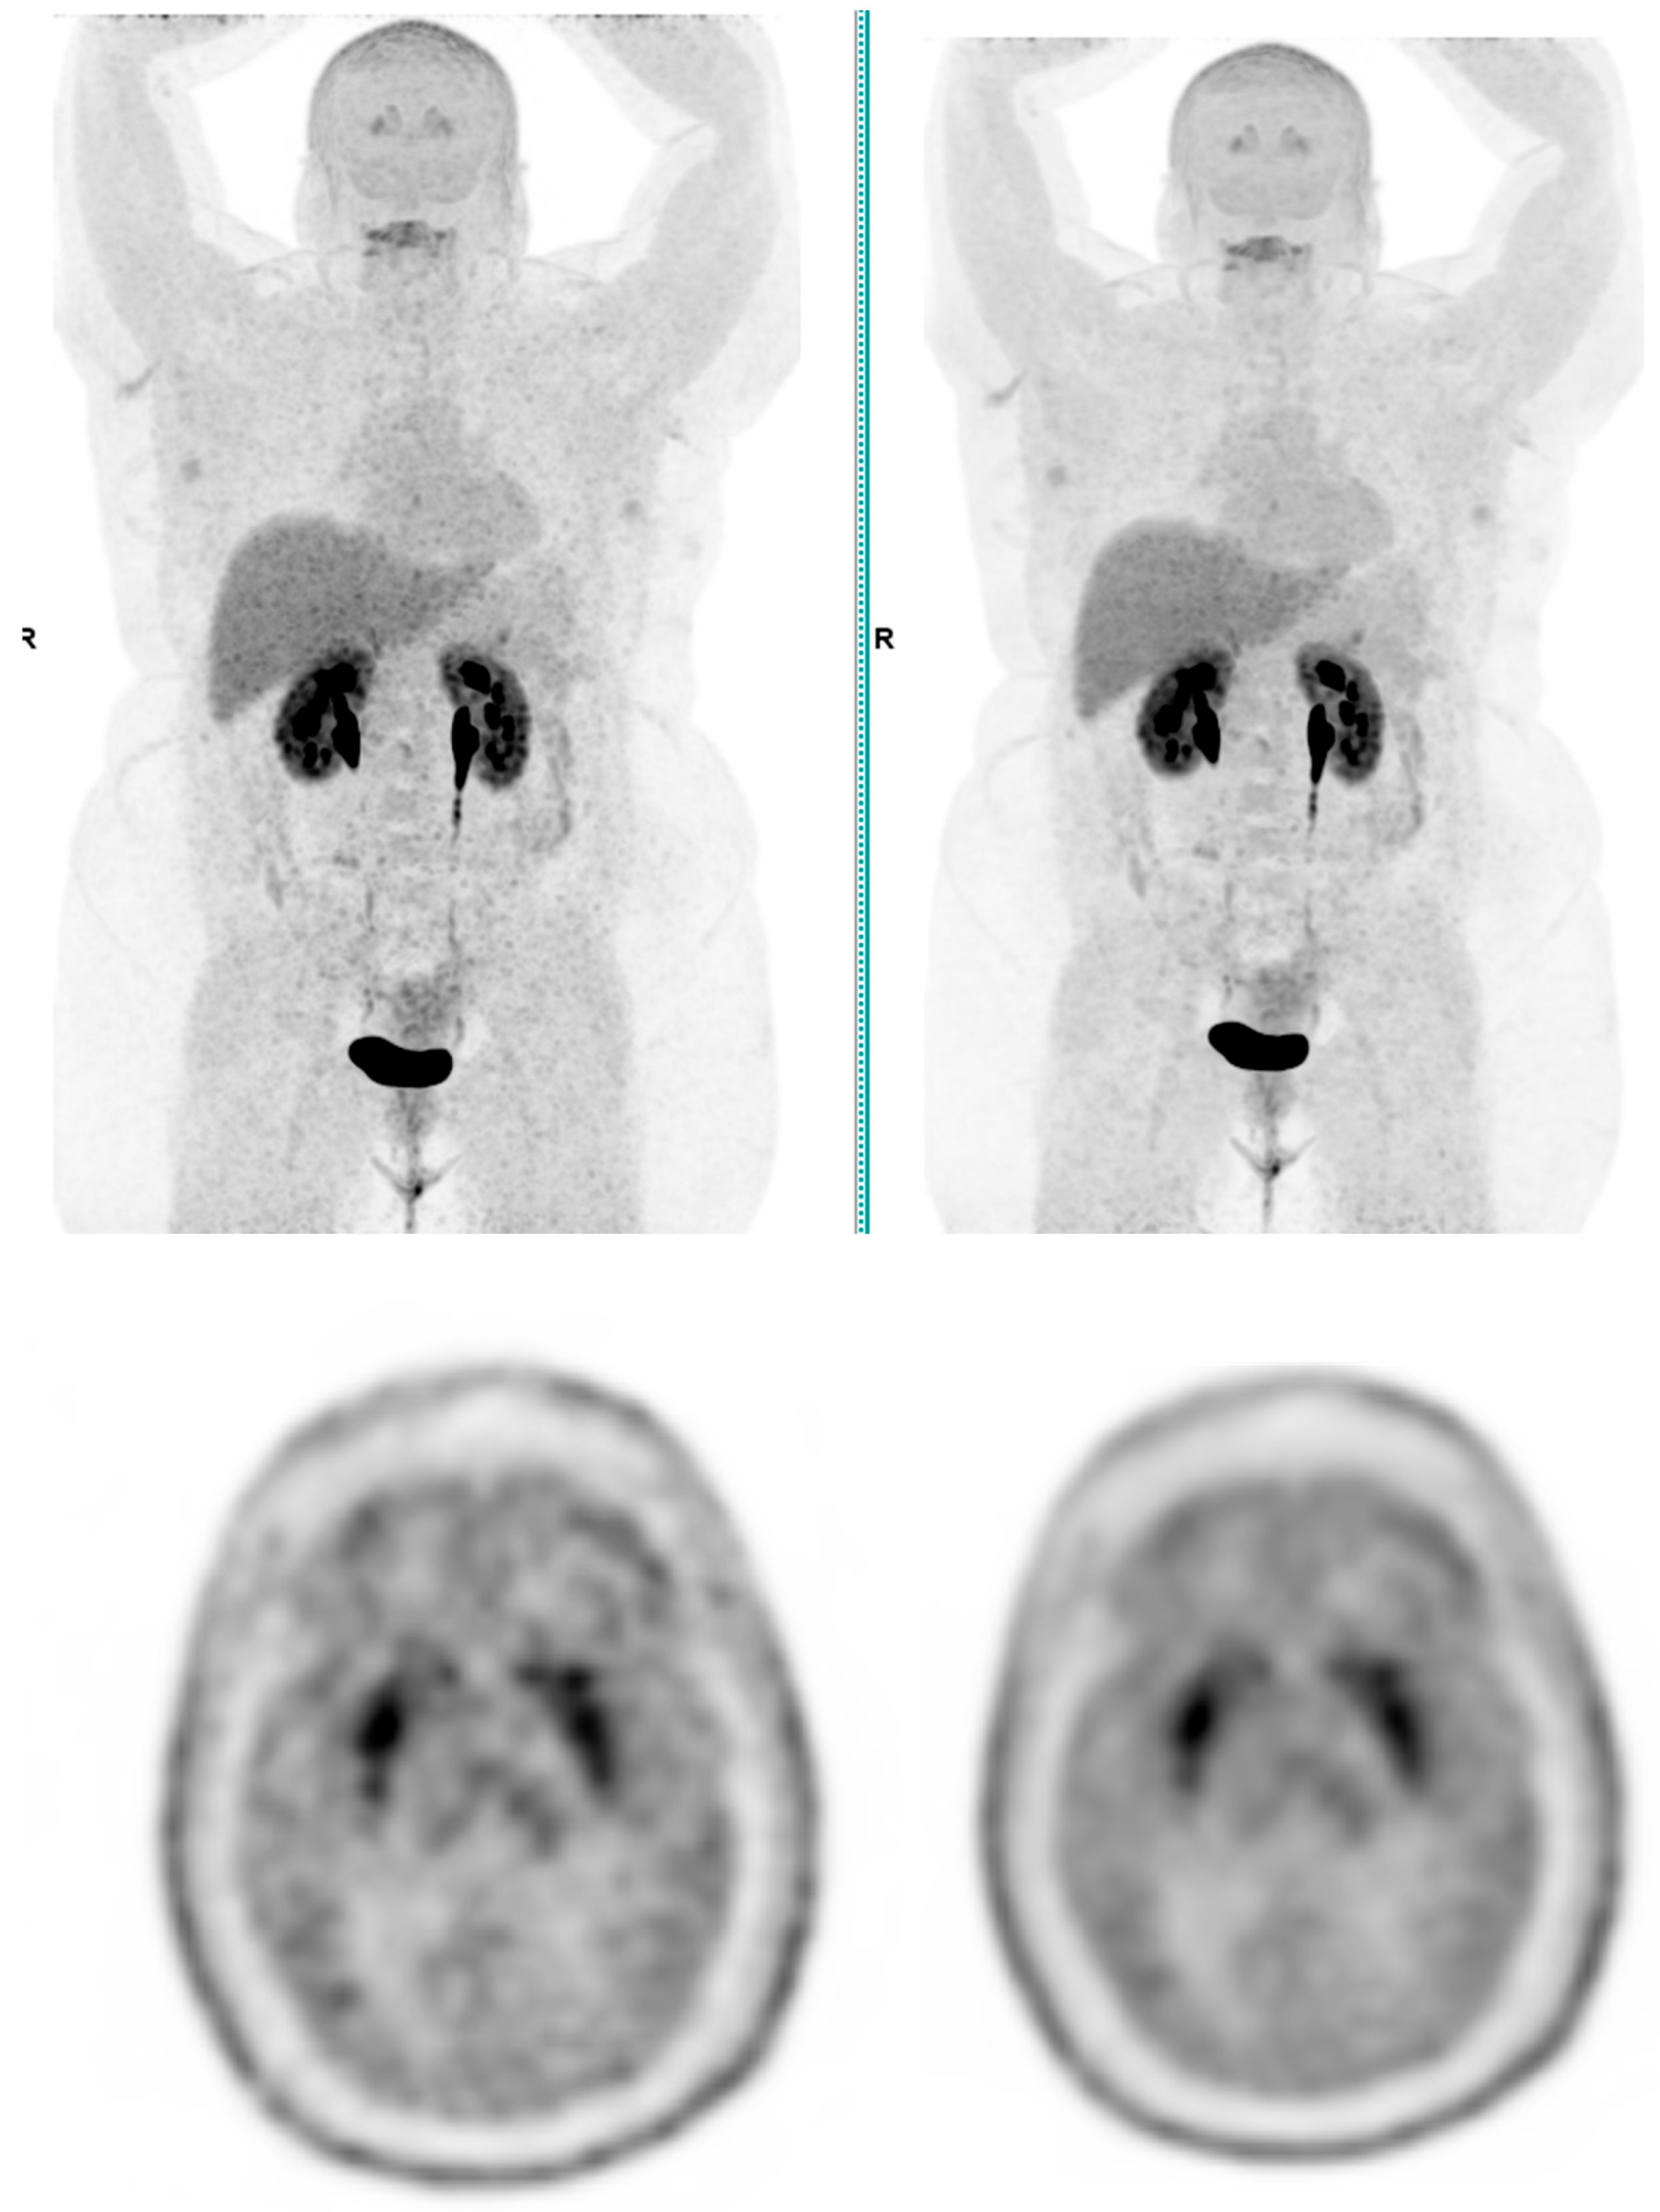

Across the three radiotracers, the AI-denoised images demonstrated a significantly improved performance in the visual analysis compared to conventional PET images. AI-denoised images were rated as interpretable (scores of 3–5) in all cases, compared to 65% for conventional images. Furthermore, an excellent image quality (score of 5) was achieved in 85% of all AI-denoised images, a significant improvement compared to the 50% in standard acquisitions. SubtlePET™ processing resulted in consistently lower noise levels, particularly for 18F-FDG scans, where 85% of images scored 4 or 5 for noise reduction compared to 60% in conventional scans. Lesion detectability was maintained or enhanced across all radiotracers, ensuring no compromise in the diagnostic accuracy. For 18F-FDOPA, a tracer with inherently lower signal-to-noise ratios, the AI algorithm improved the detection confidence by 25% compared to standard protocols. The visual comparison is illustrated through different MIP images and transaxial images (Figure 1, Figure 2, Figure 3 and Figure 4)

Figure 1. Brain 18F-FDG PET CT (left: without AI denoising; right: with AI denoising).